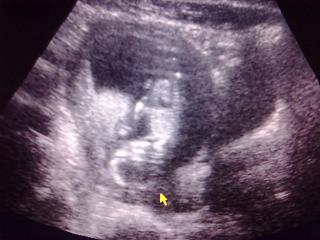

Kép

Na ő itt Ő:D

12hét +5 nap:D